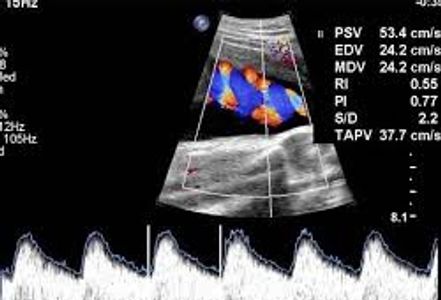

It's important to distinguish SGA (small for gestational age) babies from those with IUGR (intrauterine growth restriction). Most small babies are perfectly healthy. In fact, if we knew that all small babies are healthy, both patients and doctors might be saying the smaller the better (at least in terms of birth itself). Of course we don't say that, but it's to emphasize that size is not the issue; health is the issue (that's true after birth as well!). Most small babies are small because they were meant to be that way- it's programmed into their DNA, usually based on parent size (maternal contribution probably more important than paternal before birth). True IUGR implies that the baby is small because it's not getting enough of what it needs. A mother's diet is almost always sufficient for baby's growth, so that's not the issue. What then? The answer of course lies with the placenta- the mediator between mother and baby. If the placenta is not functioning properly then baby may not grow as is it should. In addition to smaller baby size, other clues to placental dysfunction include

Doppler studies of the umbilical artery, middle cerebral artery, and the uterine arteries can help confirm that baby is getting sufficient blood delivered to the placenta. Increased resistance of the umbilical artery Doppler can indicate growth restriction, preeclampsia, or elevated blood pressure.